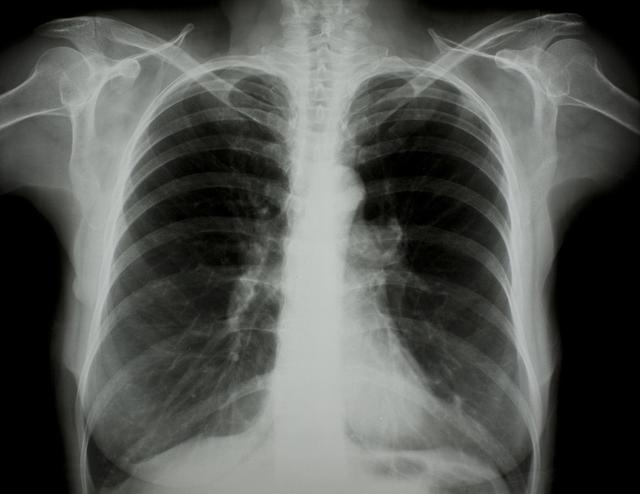

涪陵地區(qū)最新肺炎情況顯示,疫情形勢嚴峻。目前,當?shù)卣歪t(yī)療部門正在積極應(yīng)對,采取一系列措施控制疫情傳播。具體感染人數(shù)、癥狀表現(xiàn)、疫苗接種情況等仍在持續(xù)更新中。請廣大市民密切關(guān)注官方發(fā)布的信息,做好個人防護,共同抗擊疫情。涪陵地區(qū)肺炎疫情嚴峻,政府積極應(yīng)對,請市民關(guān)注官方信息,加強個人防護。

據(jù)最新官方數(shù)據(jù)顯示,涪陵地區(qū)肺炎病例數(shù)量令人擔(dān)憂,截至目前,涪陵地區(qū)累計確診肺炎病例XX例,疑似病例XX例,請大家務(wù)必提高警惕,不可掉以輕心。